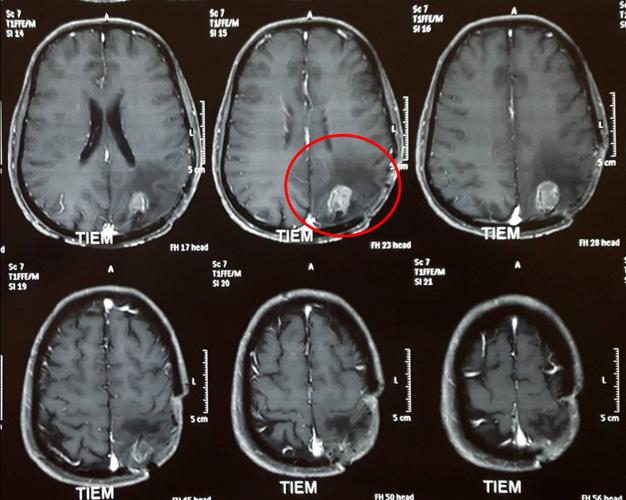

• Chụp phim cộng hưởng từ sọ não đánh giá sau quá trình điều trị cho thấy khối u thu nhỏ kích thước: 1x2 cm, còn phù não nhẹ xung quanh.

Hình 3: khối u kích thước nhỏ còn lại sau điều trị (vòng tròn đỏ)